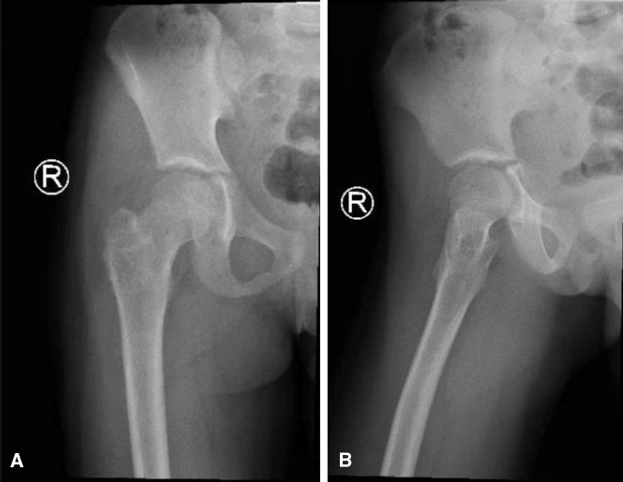

随访观察:随访期间发现,因患儿生长发育导致克氏针逐渐向股骨颈远端移位,使愈合周期延长——这恰是选用光滑克氏针而非螺钉的优势所在。图6展示了术后1年的影像资料。术后两年半,骨愈合完全,患者返院取出内固定物(图7)。内固定去除后1年随访显示(图8),股骨颈重塑至正常颈干角,末次随访时患者关节无僵硬、活动度无受限、无疼痛及跛行。